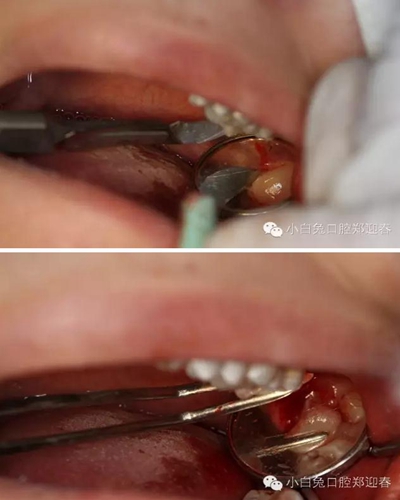

創(chuàng)口置入膠原蛋白明膠

拔除術的離體28、38

作為一名齒槽外科醫(yī)生,時刻要把安全放在第一位,盡可能做到讓患者舒適!